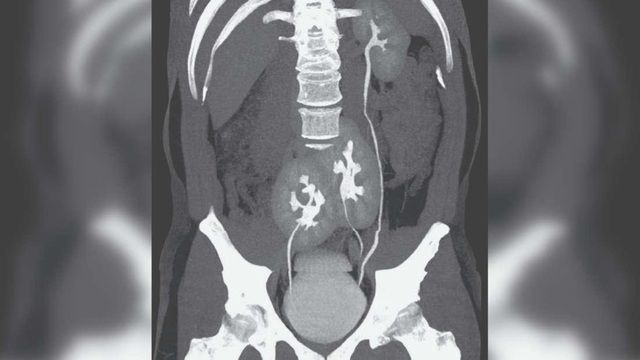

| Trường hợp hiếm gặp của một bệnh nhân ở Brazil(Nguồn: IFL Science) |

Bệnh nhân 38 tuổi này đã đến một bệnh viện ở thành phố São Paulo của Brazil khi nghi đau thắt lưng do trượt đĩa đệm. Kết quả chụp cắt lớp vi tính (CT) cho thấy, người đàn ông đang bị trượt đĩa đệm. Tuy nhiên, vấn đề này lại không được quan tâm bằng việc các bác sĩ bất ngờ phát hiện ra người đàn ông này có tới 3 quả thận. Trong đó, một quả thận trái xuất hiện bình thường và hai quả thận hợp nhất.

Nhưng kỳ lạ thay, tình trạng này dường như không ảnh hưởng đến sức khỏe của người đàn ông. Các xét nghiệm máu cho thấy, chức năng thận của bệnh nhân hoàn toàn bình thường, ngoại trừ đĩa đệm bị trượt, có vẻ mọi thứ vẫn ổn.

Thận của người đàn ông này được xác định là một bất thường bẩm sinh không phổ biến và có thể xảy ra trong quá trình phát triển phôi khi một cấu trúc giống như thận nguyên thủy tách ra làm hai.

Các bác sỹ nghiên cứu cho hay, những người gặp trường hợp này thường không có triệu chứng và họ có thể không được biết cho đến khi đi khám bệnh vì một lý do khác.